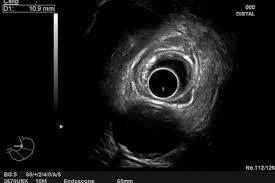

La ecografía endoscópica es un procedimiento que requiere un endoscopio especial con un transductor de ecografía en la punta. Este tipo de endoscopio se llama endoscopio ecográfico o ecoendoscopio.

El ecoendoscopio permite la realización de ecografías de alta resolución en el interior del cuerpo humano, lo que permite una mejor visualización y evaluación de los órganos y tejidos internos, como el páncreas, el hígado, el esófago, el estómago y el colon.

Durante el procedimiento, el endoscopio ecográfico se inserta por la boca o el recto del paciente y se dirige hacia el área del cuerpo que se desea examinar. El transductor de ecografía en la punta del endoscopio envía ondas de sonido de alta frecuencia que rebotan en los órganos y tejidos internos, creando imágenes detalladas en tiempo real que se visualizan en un monitor.